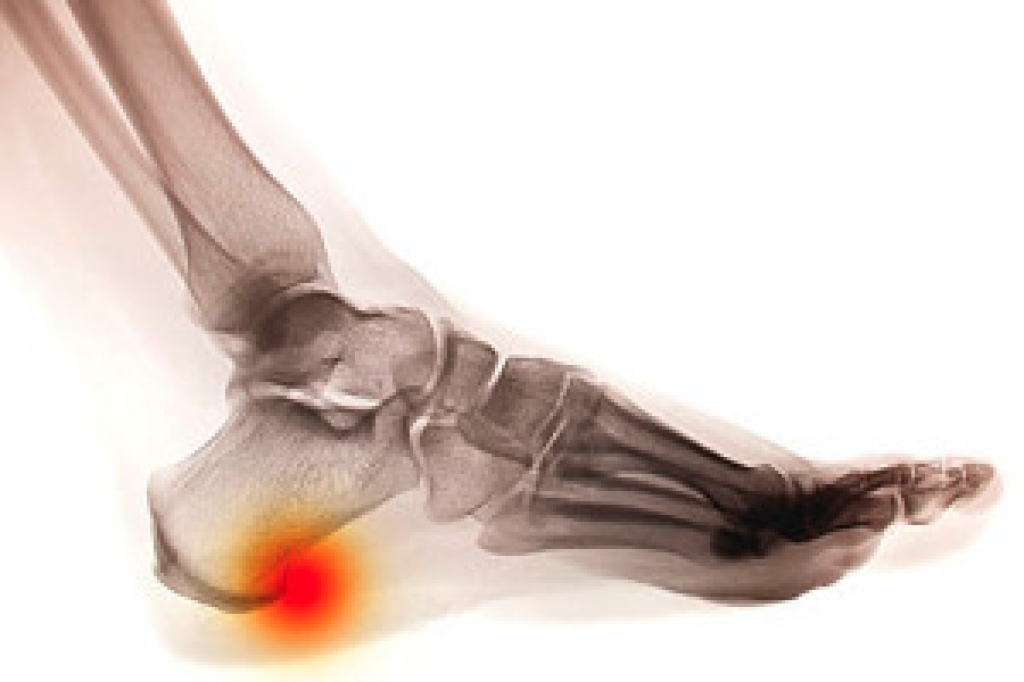

The medical condition known as a heel spur can cause severe pain and discomfort upon rising in the morning, followed by a dull ache in the heel for the duration of the day. But not everyone experiences these symptoms, sometimes people have no symptoms and only detect a heel spur as the result of an X-ray. So now you're wondering, what exactly is a heel spur? A heel spur is defined as a bony protrusion or growth that is made up of calcium and develops on the underside of a person's foot. Despite its definition, a heel spur is  usually smooth but can appear pointy or hooked. They typically develop as a result of repetitive trauma to the heel bone and existing inflammation can be connected to the pain. Mild relief may be found when resting the affected foot and it is said that performing gentle stretches can help in the recovery process as well. Some patients also find it beneficial to wear custom made orthotics as they can be helpful in providing additional support. If you are experiencing pain of any kind in your heel, it is strongly suggested that you seek the care of a podiatrist. In some cases severe heel spurs may need surgery for permanent removal, so it's best to be under the care of a foot specialist who can diagnose and treat your condition properly.

Heel spurs are formed by calcium deposits on the back of the foot where the heel is. This can also be caused by small fragments of bone breaking off one section of the foot, attaching onto the back of the foot. Heel spurs can also be bone growth on the back of the foot and may grow in the direction of the arch of the foot.

The pain associated with spurs is often because of weight placed on the feet. When someone is walking, their entire weight is concentrated on the feet. Bone spurs then have the tendency to affect other bones and tissues around the foot. As the pain continues, the feet will become tender and sensitive over time.